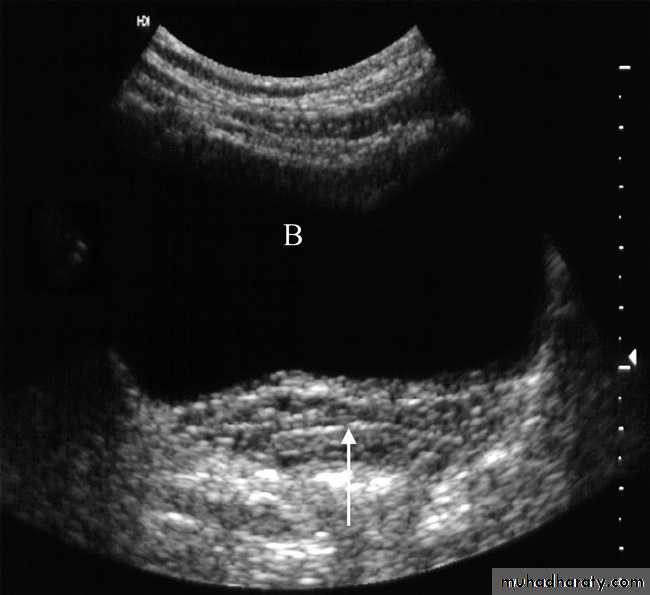

The bladder is well demonstrated on all imaging modalities. At ultrasound, the simplest routine method of imaging, the bladder lumen should be free of echogenic structures and its wall should be of uniform thickness .Bladder tumours

The bladder is the most frequent site for neoplasms in the urinary tract . Almost all are transitional cell carcinomas of varying degrees of malignancy.On ultrasound examination

bladder tumours are seen as soft tissue masses protruding into the fluid-filled bladder or as localized bladder wall thickening, . On rare occasions, there is visible calcification on the surface of the tumour, but the technique is poor for detecting extravesical spread.